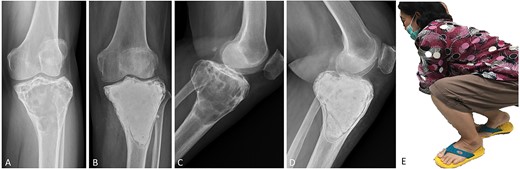

(A, C) Case no. 5: female, 23 years of age with GCTB at the distal femur without subchondral bone involvement, Campanacci grade III. (B, D) Radiograph at 81 months after extended curettage with hydrogen peroxide, phenol and cementation. (E) MSTS score 93%.

Surgical procedures were performed by two orthopedic oncology surgeons using the same surgical technique. In all cases, GCTB was confirmed by clinical data, plain radiography and magnetic resonance imaging (MRI), as well as histopathologic examination before and after surgery. Whether a medial or lateral approach was employed depended on tumor location. A large cortical window equal in size to the tumor area was created to provide visualization of the entire tumor cavity, and intralesional curettage of the tumor was performed. If the tumor extended into the soft tissue, the entire pseudo-capsule was dissected circumferentially and excised. A high-speed burr was used to extend the cavity by at least 2 mm to remove the residual tumor in all cases except those in which the lesion was in subchondral bone and cartilage. Hydrogen peroxide is the preferred local adjuvant agent at our institution, but phenol was applied along the cavity wall using gauze in three cases, and argon beam coagulator was applied in six. After the application of local adjuvant, the irrigation cavity was rinsed with saline solution. If the tumor involved subchondral bone or cartilage, hydroxyapatite bone substitution was applied 5–10-mm above subchondral bone to prevent complications from allograft and donor-site morbidity of the autogenous bone graft. We defined subchondral bone involvement as tumor location <5 mm from joint cartilage. Every part of the remaining cavity was filled with PMMA without implant augmentation or internal fixation (Figs 1–4). The large cortical window was left open with cement in most of the cases in which the cortex was destroyed by the tumor.